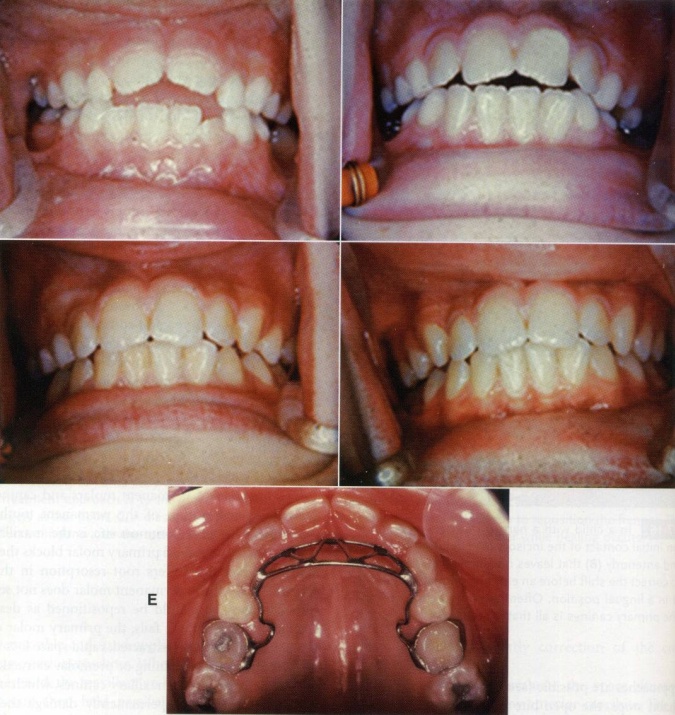

Cuối cùng, có thể sẽ phải cần dùng một khí cụ trong miệng để nhắc nhở trẻ. Khí cụ cố định thường được dùng hơn khí cụ tháo lắp. khí cụ gồm một cung lưỡi và một tấm chặn làm bằng dây thép không rỉ có đường kính lớn (0.9 – 1,0mm) được hàn vào hai khâu ở răng cối sữa thứ hai hoặc răng cối lớn vĩnh viễn thứ nhất hàm trên. Tấm chặn nhô ra (nhưng không được sắc bén) sẽ nhắc nhở trẻ không mút tay và trẻ cũng được giải thích rằng đây là vật nhắc nhở trẻ, không phải để trừng phạt trẻ để tránh gây vấn đề tâm lý cho trẻ. Sau khi trẻ ngưng mút tay, cần đeo khí cụ thêm 6 tháng nữa để đảm bảo thói quen được bỏ hoàn toàn.

Khí cụ cố định nhắc nhở trẻ không mút tay

Để điều trị hẹp hàm trên với răng cửa trên thưa và nghiêng về phía trước do mút tay, cần dùng khí cụ nới rộng hàm trên và kéo lui các răng cửa trên. Ở những trẻ có tương quan xương hàm bình thường, cắn hở sẽ đươc điều trị sau khi trẻ ngừng mút tay và các răng vĩnh viễn còn lại mọc lên.

Dụng cụ nới rộng hàm